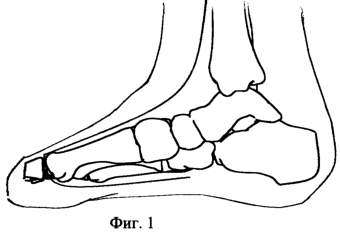

Способ осуществляют следующим образом: схема, иллюстрирующая поэтапное выполнение операции представлена на фигуре 1-3.

1. На фигуре №1 показан уровень выполненной резекции пораженного участка костного фрагмента культи первого пальца стопы.